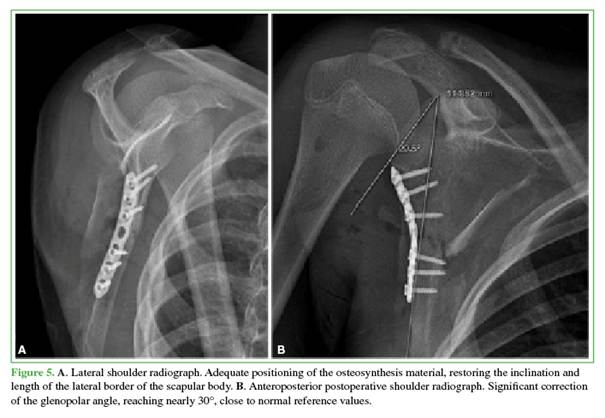

Postoperative radiographs demonstrated satisfactory alignment, with anatomic reduction and appropriate positioning of the osteosynthesis hardware. The scapular body was restored along its lateral border, improving stability at the fracture site with the pre-contoured plate in place. Improved glenohumeral alignment was noted, including restoration and increase of the glenopolar angle, correction of the inclination of the distal fracture segment, and proper alignment of the scapular body relative to the preoperative lateral radiograph (Figure 5).